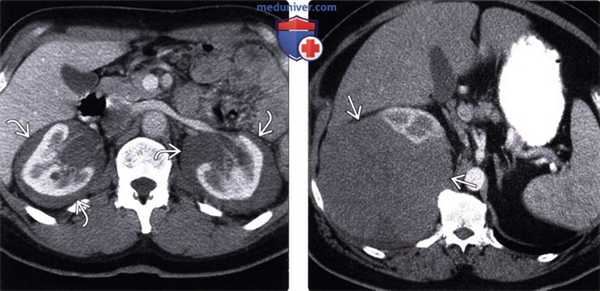

(Слева) При аксиальной КТ с контрастным усилением определяются гиподенсные мягкие ткани в виде «кожуры» вокруг обеих почек, классическое проявление периренальной лимфомы.

(Справа) При аксиальной КТ с контрастом определяется большое мягкотканное объемное образование вокруг правой почки, проявление периренальной НХЛ.

• Почки:

о Некоторые вероятные признаки лимфомы почки на диагностических изображениях:

- Единичное доминирующее объемное образование, чаще всего слабо усиливающееся при контрастировании, инфильтративного характера, однородной структуры

- Множественные двухсторонние дискретные гиподенсные объемные образования

- Одностороннее/двухстороннее увеличение почек с сохранением исходной формы и диффузная инфильтрация почек

- Мягкотканные образования вокруг почек, окружающие их в виде «кожуры»:

Могут распространяться вниз, вдоль собирающей системы почек и мочеточников, становясь причиной гидронефроза

- Контактное метастазирование в почки при заболевании забрюшинных лимфатических узлов

о Единичное доминирующее объемное образование или двухсторонние узлы

о Увеличение почек с диффузной опухолевой инфильтрацией

о Появление мягких тканей около почки, окружающих ее в виде «кожуры»